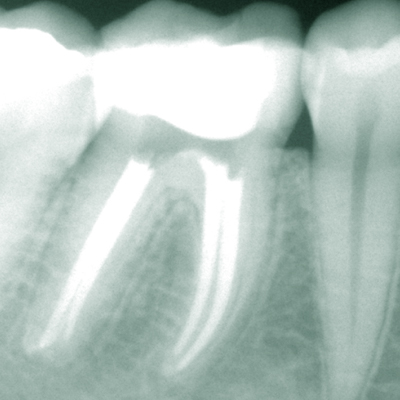

Professionell durchgeführte exakte Wurzelbehandlungen ermöglichen die Rettung eigener Zähne bei Entzündung oder nach Absterben des Gefäß-Nervengewebes (Pulpa) im Inneren des Zahnes in den meisten Fällen.Keine Angst, die Behandlung ist praktisch immer schmerzfrei. Wir verwenden sowohl für die Wurzelbehandlung als auch für Wurzelspitzenresektionen (Operation an der Wurzelspitze) modernste Techniken und neueste technische Hilfsmittel wie z.B. ein Operationsmikroskop oder ein Piezo-Ultraschallgerät. Somit können wir auch schwierige Fälle, wie Entfernen von Stiftaufbauten oder frakturierten Instrumenten, Wurzelkanalrevisionen oder komplizierte endodontisch-chirurgische Fälle lösen.